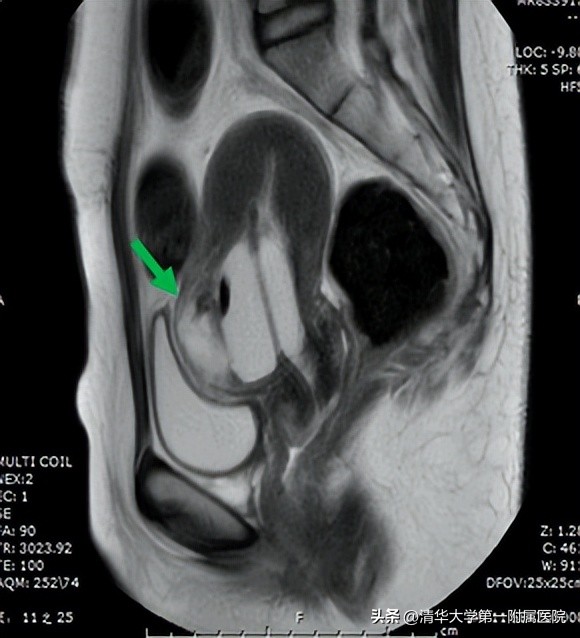

患者做MRI提示Ⅲ型剖宫产瘢痕妊娠伴早期绒毛植入(包块型)(绿色箭头指示处)

常用的治疗方法有:超声监护下清宫术、经腹或经腹腔镜、经阴道、经宫腔镜妊娠病灶切除术等方式,依据大出血的风险评级选择是否需要辅助子宫动脉栓塞术。需要结合患者的孕周、血HCG水平、超声及MRI的CSP分型、患者的生育要求等选择最适合患者的治疗方案。